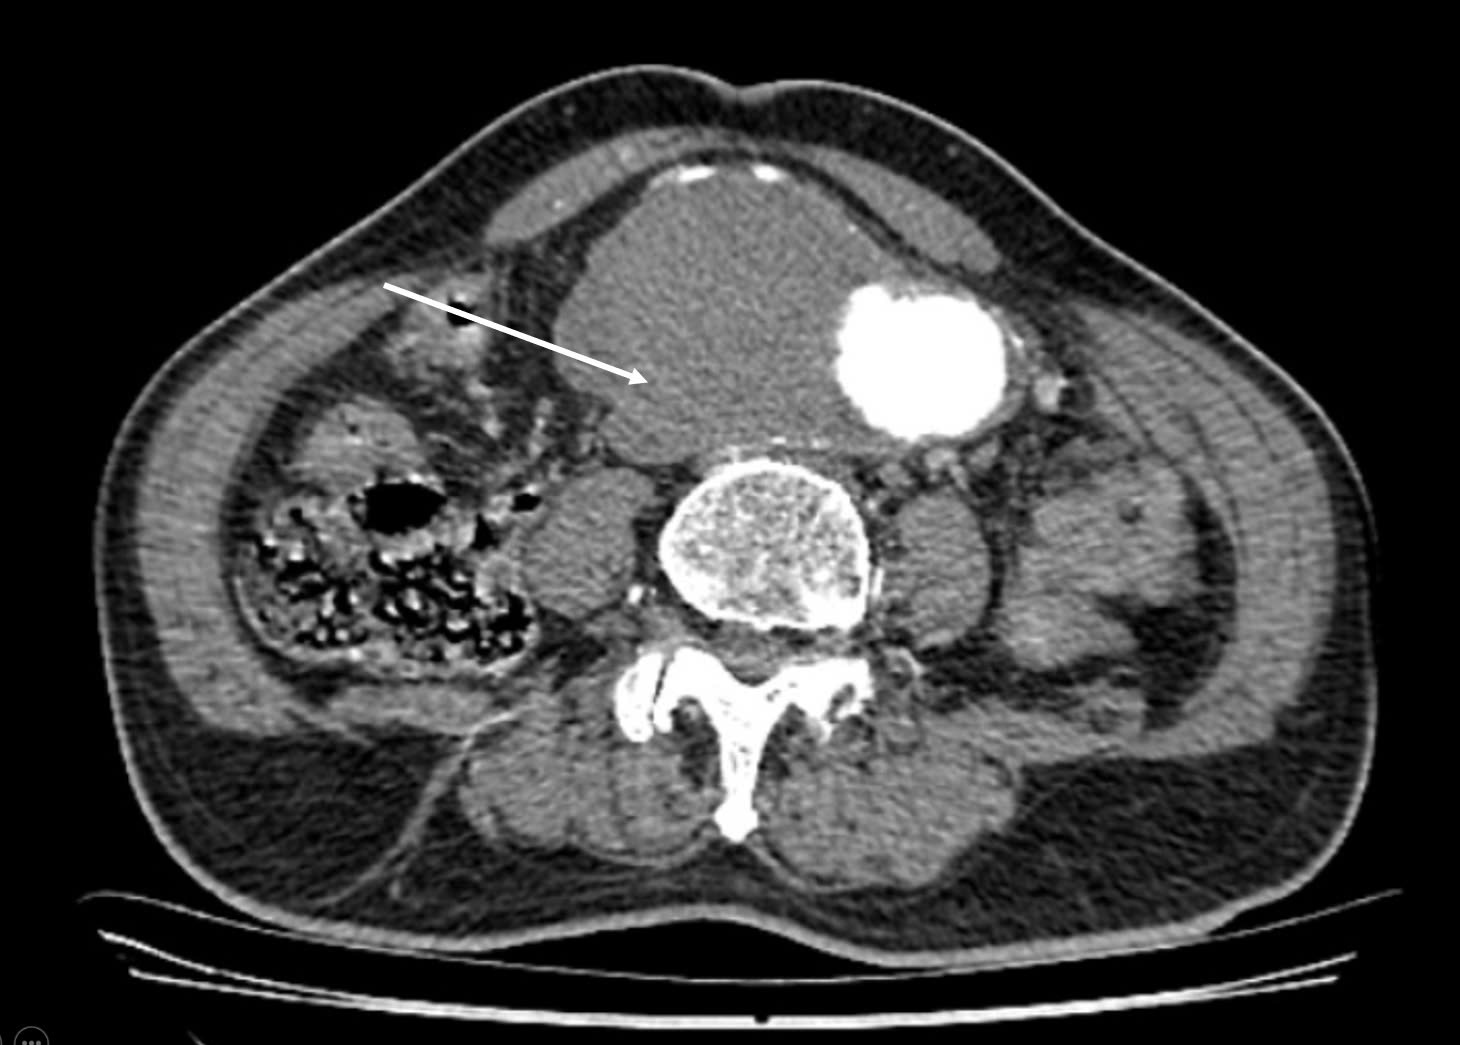

Qua thăm khám, các bác sĩ phát hiện một khối bất thường chiếm gần nửa bụng bên phải, có dấu hiệu đập theo nhịp tim. Kết quả chụp cắt lớp vi tính (CLVT) đưa ra một chẩn đoán kép cực kỳ nguy hiểm: Một khối phình động mạch chủ bụng dưới thận rất lớn, đường kính gần 9 cm, kéo dài đến tận động mạch chậu gốc hai bên và đã có dấu hiệu nứt vỡ; đồng thời, phát hiện dày thành đại tràng sigma trực tràng thâm nhiễm, nghi ngờ ung thư đại trực tràng.

Cuộc phẫu thuật kéo dài gần 5 tiếng đồng hồ. Khi mở ra, khối phình động mạch chủ rất lớn đã nứt vỡ và được đại tràng ngang, ruột non bọc lại gây dính toàn bộ, đồng thời khối u ở đại tràng sigma - trực tràng cũng rất to, thâm nhiễm và dính vào động mạch chậu hai bên.